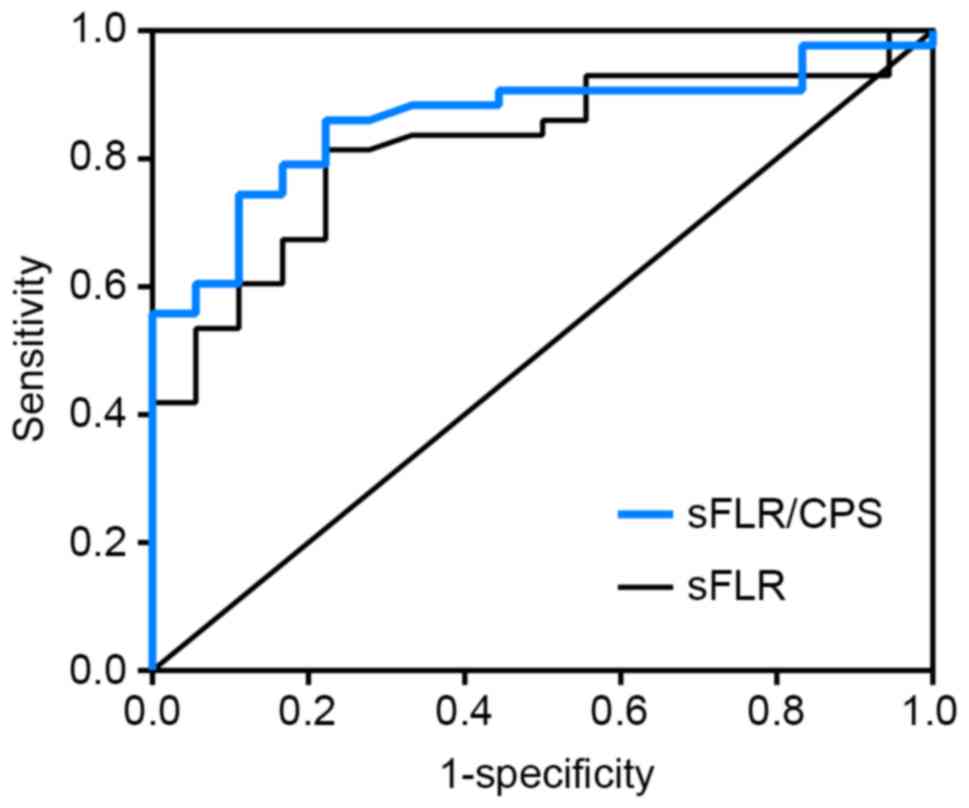

ROC curve analysis revealed that the cut-off value

of sFLR for predicting PLD was 54.5%, with 81.4% sensitivity and

77.8% specificity (Fig. 3). In total,

14 of the 22 (63.6%) patients with an sFLR <54.5% developed PLD,

compared with 4 of the 39 (10.3%) patients with a larger sFLR. This

difference was statistically significant (χ2=19.268,

P<0.001). The cut-off value of sFLR/CPS for predicting PLD was

0.0916, with 86.0% sensitivity and 77.8% specificity (Fig. 3). Of the 20 patients with an sFLR/CPS

of <0.0916, 14 (70.0%) developed PLD compared with 4 of 41

(9.8%) patients with a higher sFLR/CPS, and this difference was

statistically significant (χ2=23.455, P<0.001). This

result indicates that sFLR/CPS was a more useful predictor of PLD

in HBV-related HCC patients following hepatic resection compared

with sFLR alone.